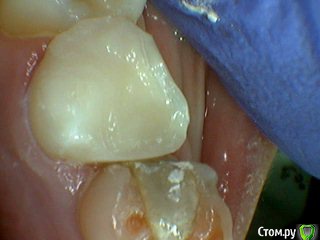

Давлетшин Опубликовано 29 декабря, 2017 Поделиться Опубликовано 29 декабря, 2017 (изменено) Друзья. Расскажите, не поменялось ли ваше отношение к пульпотеку и пр.Почему пломбы поверх пульпотеку такие ужасно жёлтые? Что сделать можно. Или что я делаю не так? "Друзья" так приятно перед новым годом. К пульпотеку не поменялось (устраивает вполне) , к пульподенту скептическое отношение, хоть и тоже работаю. Пломбы сразу желтые или через полгода - год- два? Очень тяжело что то советовать он лайн не видя как человек работает. В фото первая цифра пациент, вторая-третья номер зуба, четвертая порядок фото. Я после наложения пульпотека , стараюсь убрать излишки, или аккуратно на устья каналов накладываю, в пульповую камеру СИЦ, и сверху пломбу, Убрать излишки и со стенок, аккуратно в том числе и бором. В третьем клиническом случае, неудача. Зуб удалил сам же через 3 месяца. причину вижу в том что на рентгене не увидел (или так сделали снимок?) вертикальный тип рассасывания практически до бифуркации., может и потому что ребенок ОЧЕНЬ плохо сидел. За фото не пинайте сильно, не инстаграмм все таки,да и тяжело ребенка лечить и фотки делать. или наоборот пинайте может лучше начнем фоткать. P.s. Добавлю протокол как лечу с пульпотеком, хр.фибр.пульпит1. анестезия2. кофер ( если дает)3. раскрытие кариозной и пульповой камеры4. удаление коронковой пульпы маленьким эскаватором, я стараюсь "отрубать" пульпу5. остановка кровотечения сухим ватным шариком, 0,5-1-2 минуты6. пульпотек на устья7 СИЦ в пульповую камеру8 со стенок остатки пульпотека соскребаю бором фиссурным , цилиндрическим, там же фальц9. Пломба. может что то и зыбыл ну и оценка только позитивная перед НГ Изменено 29 декабря, 2017 пользователем Давлетшин 2 Ссылка на комментарий